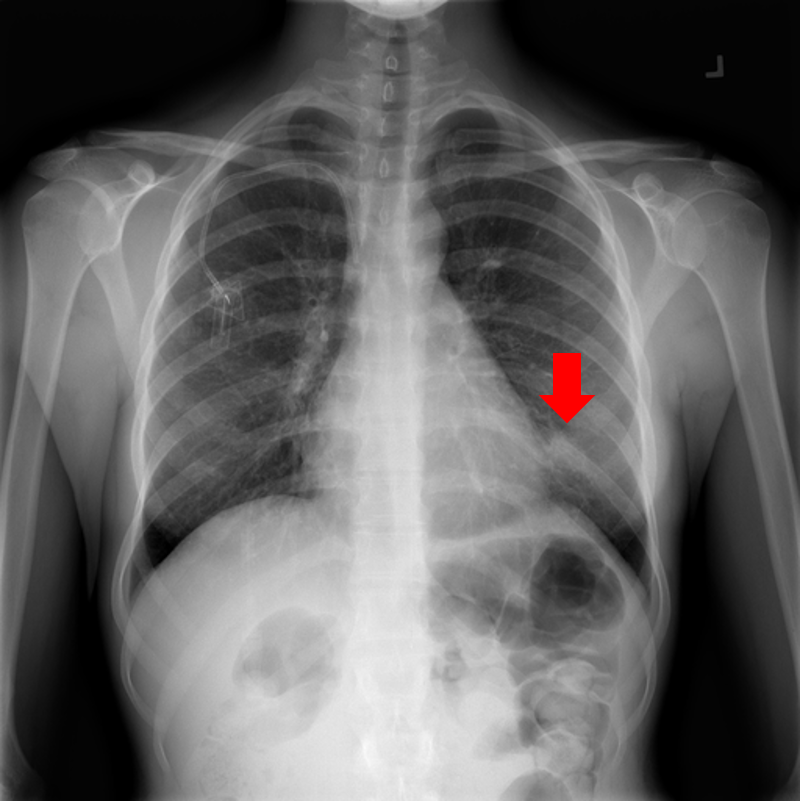

Refer to caption

Figure 9: Typical CXRs with pneumonia-like lung opacity from among the top 1,000 CXRs most likely to have an abnormality according to the logarithm posterior probability out of the 13,863 abnormal CXRs. The lesion is indicated with a red arrow if applicable.

Figure 9 shows CXRs suggested to have pneumonia-like lung opacity with the logarithm posterior probability. These CXRs are the top 1,000 CXRs most likely to have an abnormality out of the 13,863 abnormal CXRs.